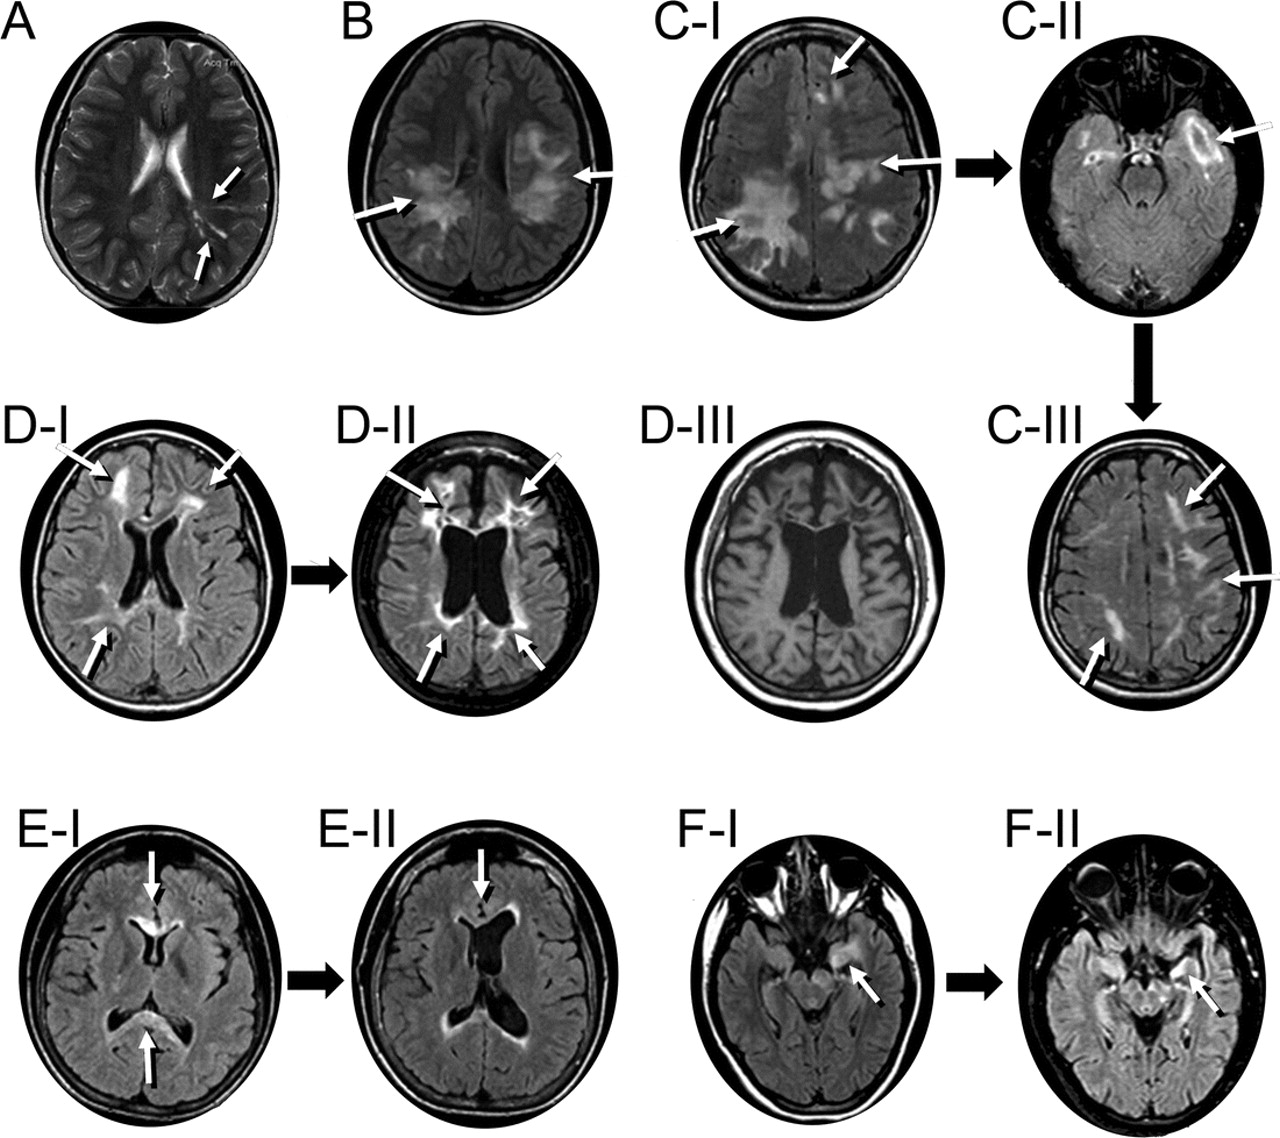

图3七个孩子代表MRI异常显示出脑干的频谱,周围,peri-IVth心室和脊髓参与地区已知高度表达aquaporin-4

白色的箭头表示异常液体衰减反转恢复或T2信号。冲黑色线条代表解剖水平关系图。(一)病人5(17岁的女孩;另请参阅图1中,E通过我)两国在上级小脑的病变总花梗(ⅰ),在小脑白质病变(A-II)和双边病变内部胶囊(A-III)。四年后病人出现症状性阻塞性脑积水(iv,也看到图1E-II;内囊损伤已经解决)。(B)病人8(11岁女孩)纵向广泛T2在中央脊髓异常通常是发现在成年neuromyelitis视(在本例中11椎段)。(我)病人9(17岁的女孩出现棘手的呕吐,四肢瘫痪,补剂肢体痉挛)和(C-II)病人11(17岁的女孩出现棘手的呕吐)纵向跨越脑干损伤和中央颈,胸线。